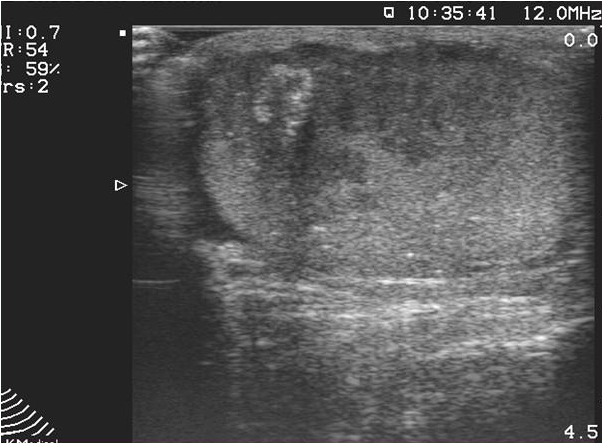

Ultrasonography (US), which is an extensively used and a widely available method, is often the first step in the diagnostic work up. During a regular abdominal US scan both kidneys are examined. Sensitivity of the US examination is significantly lower than of a CT scan, still important clinical questions can be answered with this technique. When a tumor is visualized, it is usually a hypoechoic, relatively well circumscribed mass.

Image

Figure 3. Kidney tumor on US